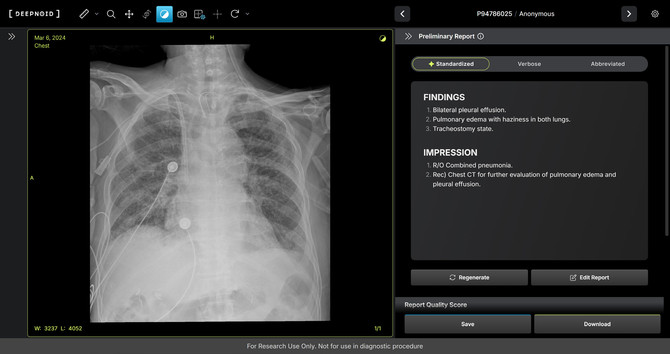

'M4CXR'은 흉부 엑스레이(X-ray) 영상에서 41종의 병변을 판독해 수초 만에 일관성 있고 신뢰성 높은 판독소견서 초안을 작성한다. 이는 흉부 엑스레이 영상과 대응되는 1000만 건 이상의 판독소견서 데이터를 학습해 구현된 기술이다.

특히 응급상황에서 의료진이 즉시 예비 판독 결과를 받을 수 있어 중요한 임상 결정과 환자 진료에 더욱 집중할 수 있도록 지원하며 영상의학과 전문의의 판독을 보조한다.